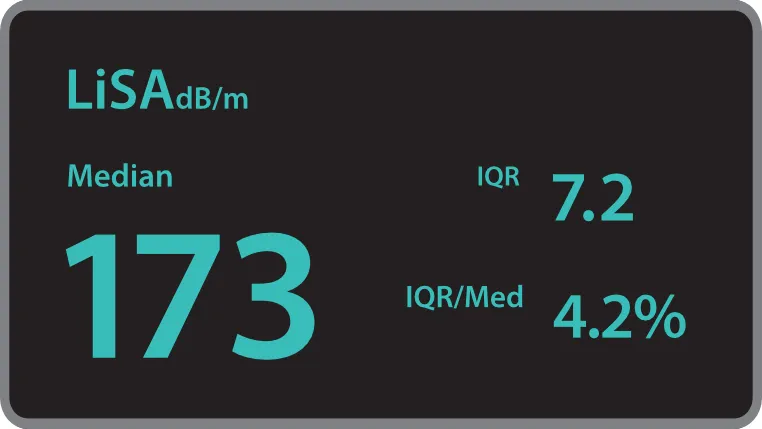

Количественный анализ ригидности печени Обеспечивает количественное определение жесткости печени и стадии фиброза печени с помощью технологии переходной эластографии

Количественный анализ ригидности печени Обеспечивает количественное определение жесткости печени и стадии фиброза печени с помощью технологии переходной эластографии Количественный анализ стеатоза печени Количественная оцененка тяжести стеатоза печени с помощью технологии LiSA (поглощения ультразвука в печени).

Количественный анализ стеатоза печени Количественная оцененка тяжести стеатоза печени с помощью технологии LiSA (поглощения ультразвука в печени).